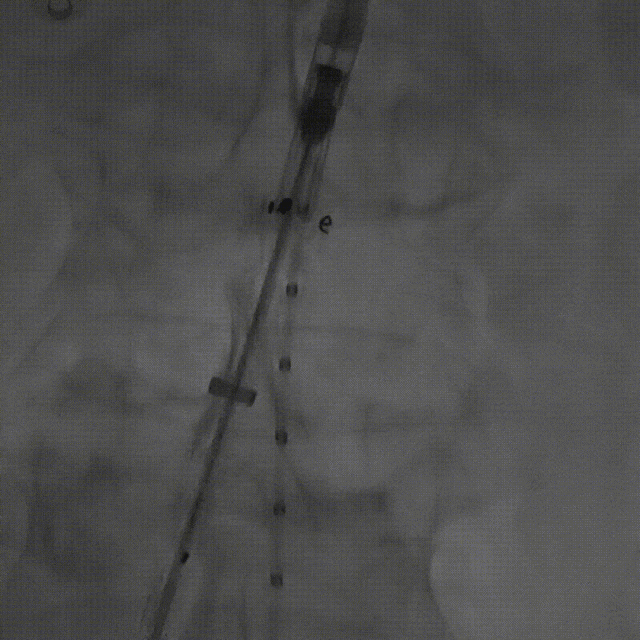

该技术主要适用于采用旋转式释放机制的支架。其核心操作步骤为:在主体支架释放出前2-3节后,轻微松开支架,然后反复反向旋转并上推输送鞘。 这一动作能促使已释放的近端支架段在瘤颈处产生可控的“堆叠”效应,从而更好地顺应瘤颈的弯曲形态,尤其是在大弯侧实现更紧密的贴壁,有效拓展了功能性密封区。

案例一(巨大成角瘤颈):患者瘤颈虽长但呈90度成角。在完成髂动脉重建后,采用Reverse技术释放主体支架。术中造影显示,支架完美贴合扭曲的血管大弯侧,术后一月复查CTA,原有的少量内漏已完全消失。

案例二(短瘤颈+梯形瘤颈):患者近端瘤颈长度不足1cm,且伴有大量附壁血栓。选用适当oversize的支架,结合Reverse技术释放,支架主体自动“寻找”并适应最佳的贴附区域,最终造影显示无明确内漏。

截至目前,采用Reverse技术处理不良瘤颈的初步经验(21例)显示,术中发生明显I型内漏仅3例,其中2例经弹簧圈栓塞处理,1例在随访中自行消失。这表明Reverse技术在处理不良瘤颈时,是一种安全、有效且能显著减少内漏发生的手段。